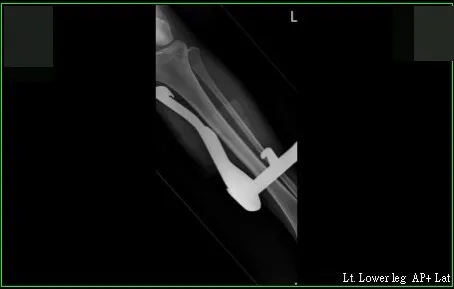

收治李小姐的高雄市立大同醫院整形外科主任賴雅薇表示,李小姐到院馬上被送進開刀房,在X光片下,可看到尾部有倒勾、長達23公分的中柱,整隻插在李小姐的左腿裡,「整個開刀房人員都圍過來看」。

在X光片影像中,可看到長達23公分的中柱,直直插在李小姐左腿裡。讀者提供